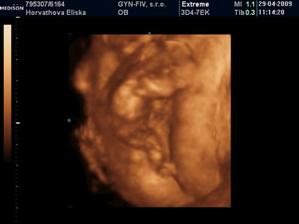

Dvojicky po KET